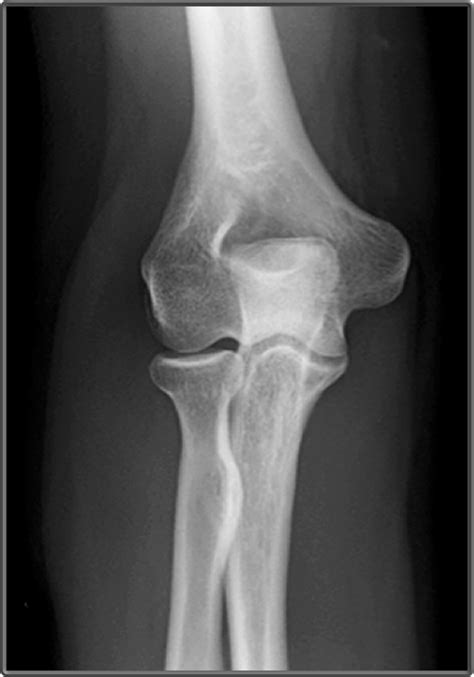

First things first: what is an AP elbow X-ray? AP stands for anteroposterior , which refers to the direction of the X-ray beam. In an AP view, the X-ray beam passes through the front (anterior) of your elbow and exits through the back (posterior). Think of it like shining a flashlight through your elbow from the front. The image captured shows a two-dimensional representation of the bones and soft tissues within your elbow. This view is one of the standard ways doctors visualize the elbow joint, helping them diagnose a wide range of conditions. It’s a non-invasive procedure, meaning it doesn’t involve any incisions or injections, and it’s generally quick and painless. Usually, an AP view is combined with other views, such as a lateral view, to get a comprehensive picture of the elbow. The AP view is particularly useful for visualizing the alignment of bones, detecting fractures, and assessing the overall structure of the elbow joint. It’s a crucial tool in the hands of radiologists and orthopedic specialists. The AP elbow X-ray gives an overview of the elbow joint, so the professionals can make better diagnoses.

Now, let’s get to the juicy part: what do the images actually reveal? The AP view shows a two-dimensional picture of your elbow. Here’s what you can see and what doctors look for:

• Bones : The AP view clearly shows the bones of the elbow joint: the humerus (upper arm bone), the radius and ulna (forearm bones). Doctors examine these bones for fractures, dislocations, or any other abnormalities.

• Joint Space : The space between the bones in the joint (the joint space) is visible. Narrowing of this space can indicate arthritis.

• Alignment : The AP view allows doctors to assess the alignment of the bones. Proper alignment is essential for normal elbow function.

• Soft Tissues : Although not as detailed as other imaging methods like MRI, the AP view can sometimes show soft tissue changes, such as swelling or the presence of foreign objects.

• Fractures : The most obvious thing to look for is fractures, which appear as breaks or cracks in the bones. The radiologist will carefully examine the bones for any signs of these fractures.

• Bone Spurs : Doctors can see the bone spurs that can develop due to arthritis or other conditions.

Interpreting an AP elbow X-ray requires expertise. Radiologists are trained to identify subtle changes and abnormalities that might not be obvious to the untrained eye. They will use their knowledge and experience to provide a detailed report to your doctor, which will then guide your treatment. If you have any medical condition, the AP view will help the doctors to get a better diagnosis.